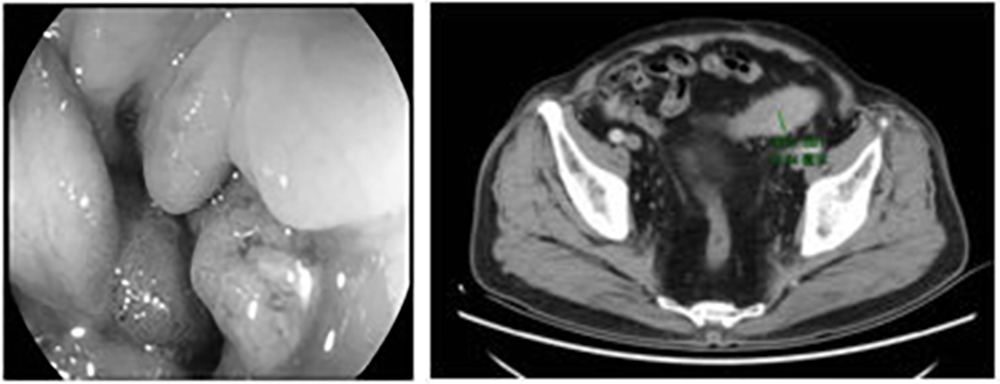

患者李XX因“便中带血5天”入院,经过详细查体、完善检查后,肠镜见距肛门约17cm可见环周隆起型肿物,表面粗糙,易出血,病变致肠腔明显狭窄,电镜无法通过,距肛门约14cm见隆起型病变,活检病理结果为恶性。患者同时患有严重的心肺功能障碍:冠状动脉左前降支重度狭窄(84%),右冠状动脉中度狭窄(54%),24小时动态心电图提示持续房颤,肺通气功能提示重度限制性通气功能障碍。患者手术指征明确但手术风险极大。院长王茂楠带领团队详细讨论,制定了详尽围手术期治疗方案,并组织麻醉科、重症监护病房、综合内科、内五科、放射线科进行了术前多学科会诊,严把患者治疗过程中的每一关,对患者病情进行详尽讨论后,决定施行创伤小、出血少、恢复快的腹腔镜乙状结肠癌根治术。